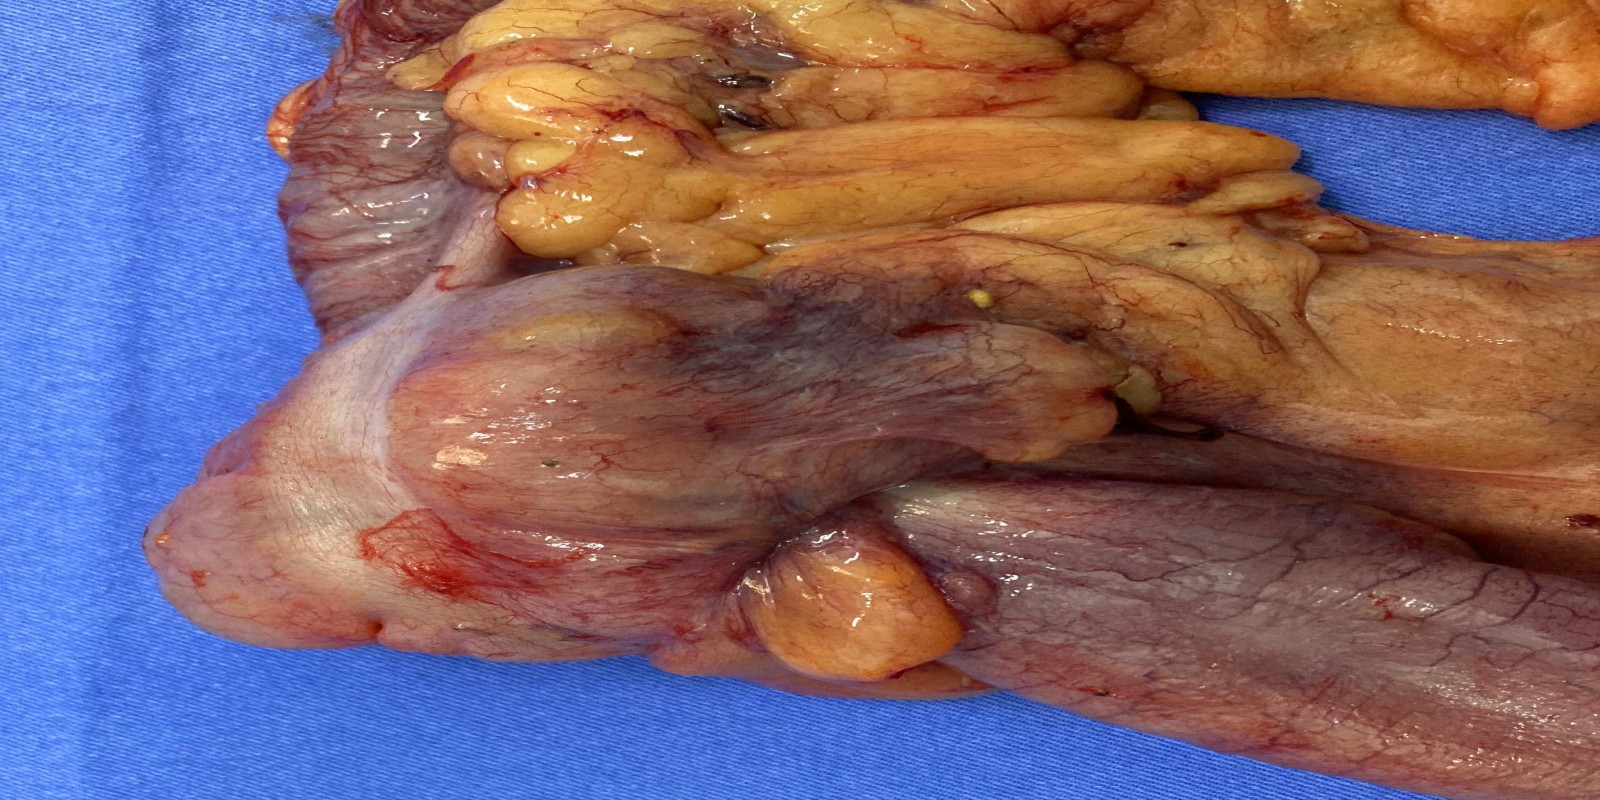

Caso Código 267C de Intussuscepção

Cod.: 267C